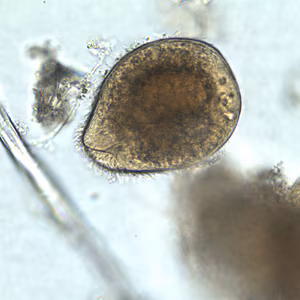

A 45-year-old pig farmer from rural Georgia presented to his health care provider with abdominal pain, cramps and diarrhea. Stool specimens were collected in polyvinyl alcohol (PVA) and 10% formalin for ova and parasite (O&P) examination. The objects in Figures A and B, which measured on average 90 micrometers in length, were observed in low numbers in formalin-concentrated wet mounts of the stool. The objects in Figures C and D, which measured on average 12 micrometers in diameter, were seen in moderate numbers on trichrome-stained slides prepared from the PVA-preserved stool. What is your diagnosis? Based on what criteria?

Figure A